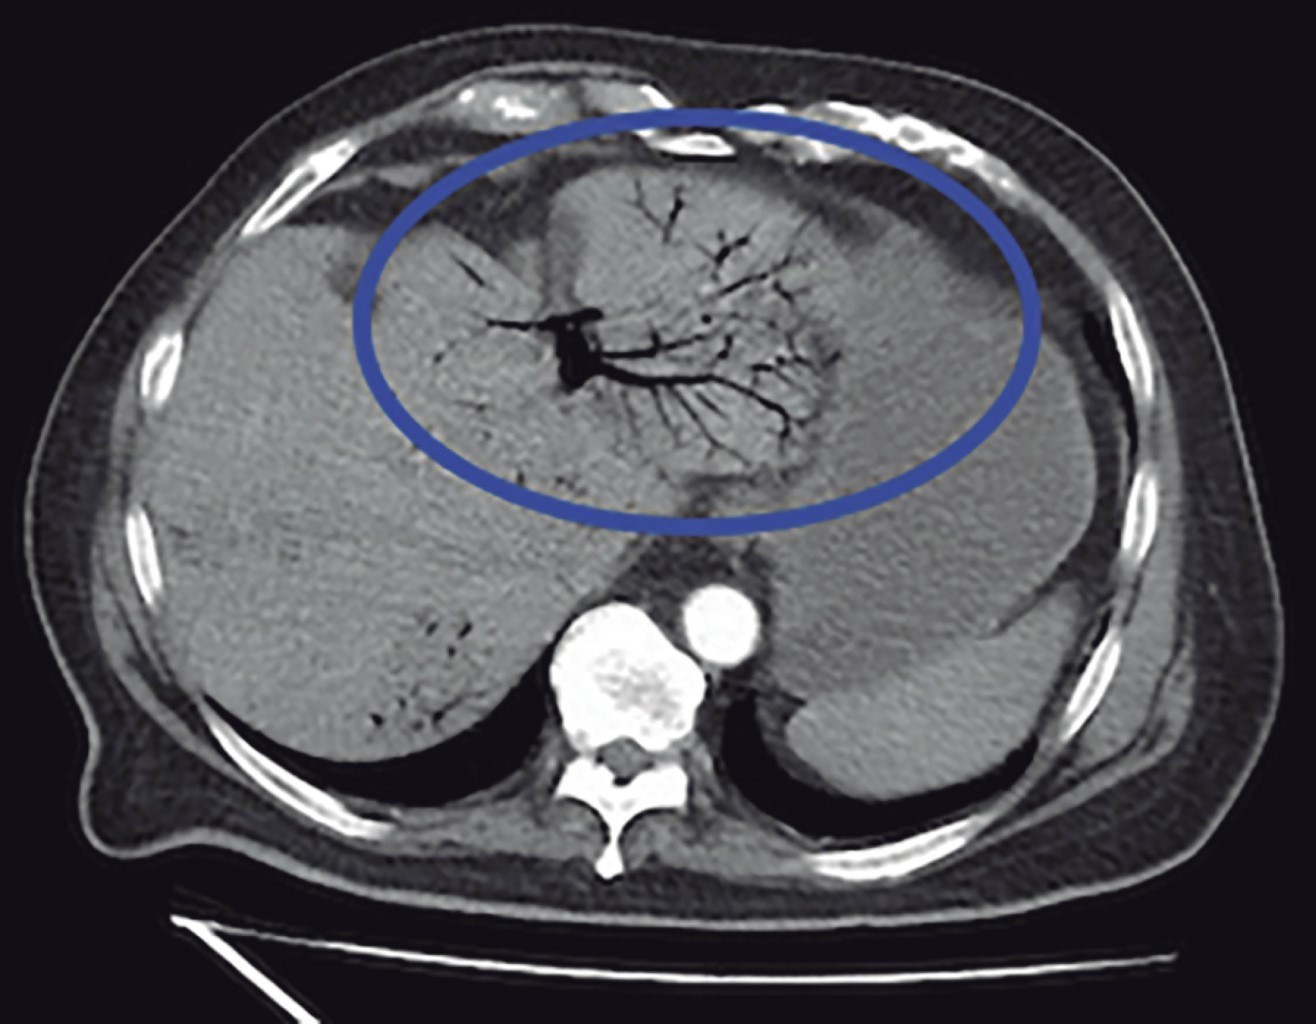

We present the case of a 77-year-old male with a history of diabetes mellitus 2 and long-standing systemic arterial hypertension, surgical history of laparoscopic cholecystectomy six years ago, and cardiac catheterization for chronic ischemic heart disease. His current condition began 10 days before his admission with diffuse abdominal pain in the lower quadrants, as well as an attack on his general condition accompanied by asthenia and hyporexia. An external physician with antibiotic therapy managed him. On arrival at the Emergency Department, he presented tachycardia and a tendency to hypotension accompanied by altered alertness. Physical examination revealed an inflammatory plastron in the left lower quadrant that aroused pain during manipulation; however, there was no evidence of peritoneal irritation. Laboratory tests showed leukocytes 13,400 mm3, neutrophilia 92.9%, and lactate 3.9 mmol/l. A contrast abdominopelvic CT scan was requested, showing portal vein thrombosis (Figure 1), portal pneumatosis (Figure 2), and diverticular disease (Figure 3). Due to the above findings, initial management with intravenous solutions and empirical broad-spectrum antibiotic therapy with piperacillin-tazobactam 4.5 g IV every 8 hours was started; after stabilizing management, exploratory laparotomy was performed, where sigmoidectomy and terminal colostomy were performed due to the findings of diverticular perforation (Figures 4 and 5) and purulent inflammatory plastron in the mesosigmoid with special distribution in the path of the inferior mesenteric vein. Samples for cultures were taken. Postoperative management was performed in the intensive care unit, and antibiotic therapy was directed to E. coli. Total parenteral nutrition and anticoagulant therapy were started with 60 mg of enoxaparin subcutaneously (SC) every 12 hours. The patient had a favorable clinical evolution thanks to the multidisciplinary management provided. He was discharged one week after the surgical procedure without any complications. He was referred to the outpatient clinic one week after his discharge. He was tolerating the oral route with a functional stoma and with the wound intact. The histopathology report revealed a complicated diverticular disease.

Figure 1